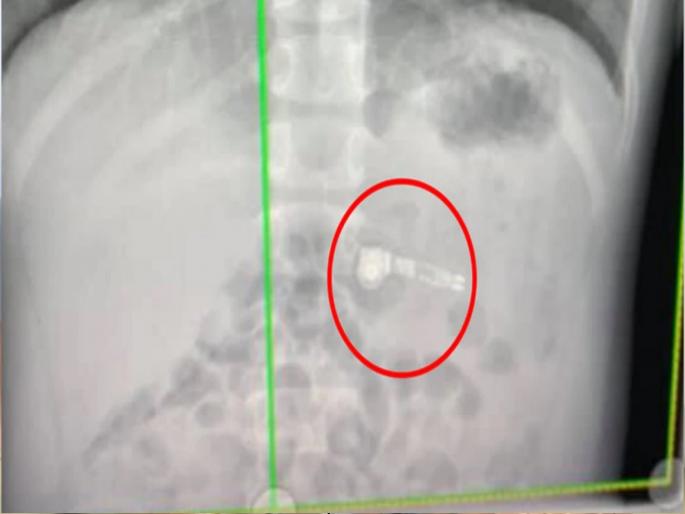

टिकटॉकवर @iamcarliiiib यूजरनेम असलेल्या महिलेने कथितपणे औषधाऐवजी तिचा एक AirPod गिळला. ही घटना एक वर्षाआधीची आहे. महिलेने सांगितलं की, तिला पेनकिलर इब्रुप्रोफेन घ्यायची होती. जी तिच्या हातात होती, तर दुसऱ्या हातात आयपॉडचा एक भाग होता. वेदना होत असताना तिने घाईघाईत औषधाजागी एअरपॉड गिळला. काही सेकंदात तिची चूक तिच्या लक्षात आली. तिने एअरपॉड बाहेर काढण्याचा प्रयत्न केला. पण त्यात काही यश आलं नाही. एक्स-रे काढल्यानंतर कंफर्म झालं की, एअरपॉड तिच्या पोटातच आहे.